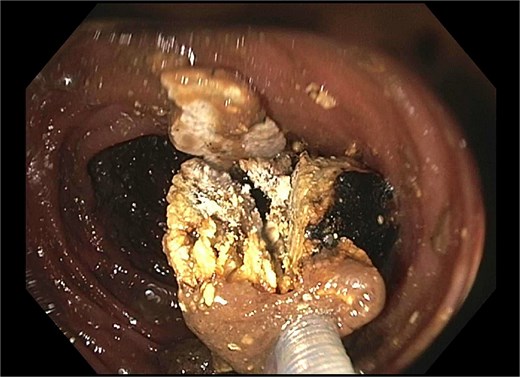

He re-presented 10 days later with nausea, vomiting, and obstipation. CT imaging showed large bowel dilation and a 3–4 cm gallstone lodged in the proximal sigmoid colon (Fig. 2). Flexible sigmoidoscopy confirmed the presence of the stone at a diverticular stricture (Fig. 3). Initial endoscopic retrieval attempts using snare, Roth net, and EHL failed.

Endoscopic view of gallstone impacted at diverticular stricture.

A subsequent attempt with a dual-channel colonoscope allowed for mechanical lithotripsy via trapezoid basket, successfully fragmenting the stone (Figs 4–6). The patient resumed a regular diet, passed flatus and stool, and was discharged with outpatient follow-up for elective cholecystectomy.